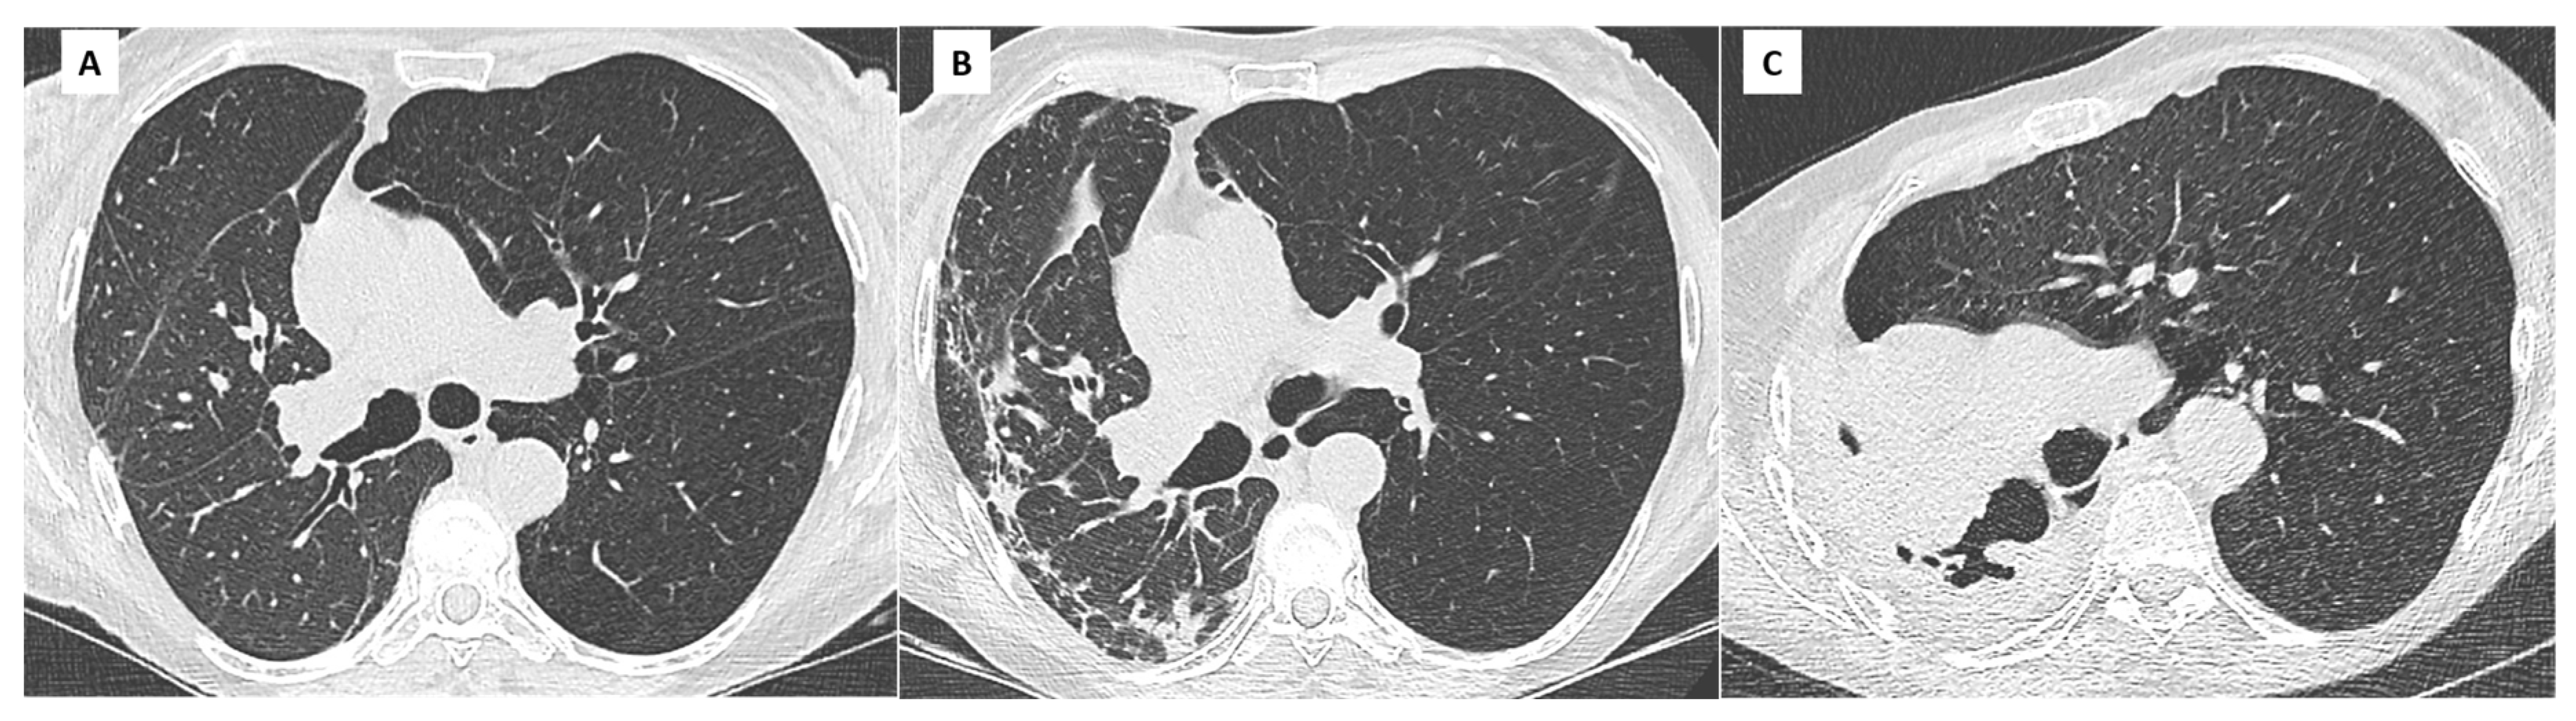

4. Bronchiolitis Obliterans Syndrome